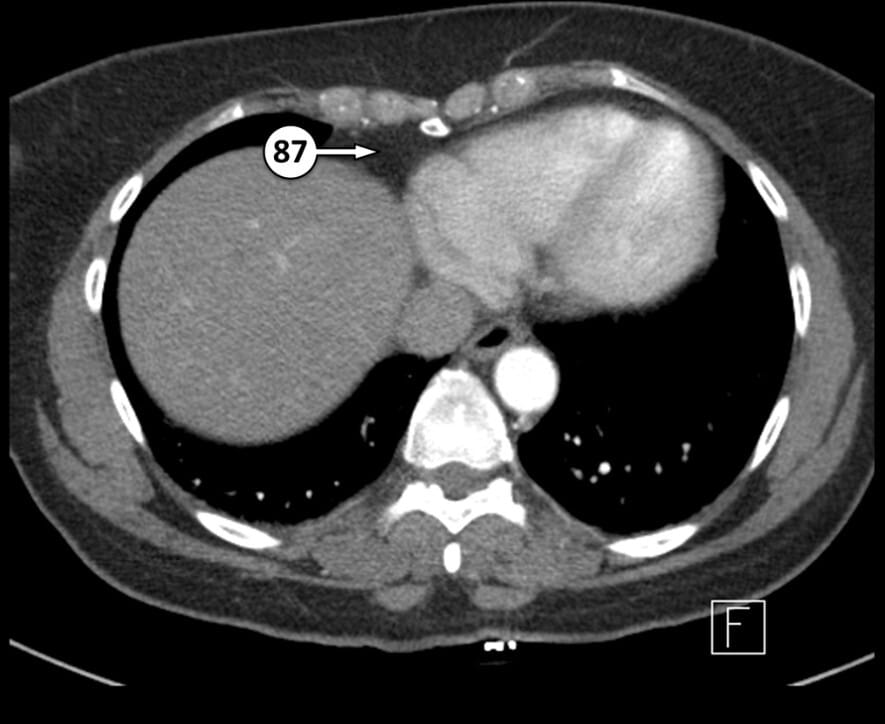

87. right pericardial fat pad